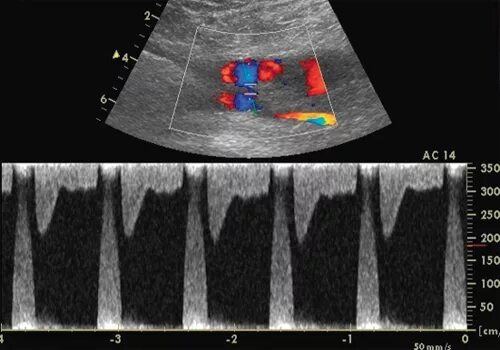

Пульсирующая гематома узи. пульсирующая гематома бедренной артерии после стентирования. пульсирующая гематома и ложная аневризма. пульсирующая гематома общая хирургия.

Постпункционная гематома. пульсирующая гематома бедренной артерии. пульсирующие гематомы. пульсирующая гематома узи.

Пульсирующая гематома бедренной артерии после стентирования. пульсирующая гематома узи. пульсирующая гематома бедренной артерии на узи. пульсирующая гематома узи протокол.